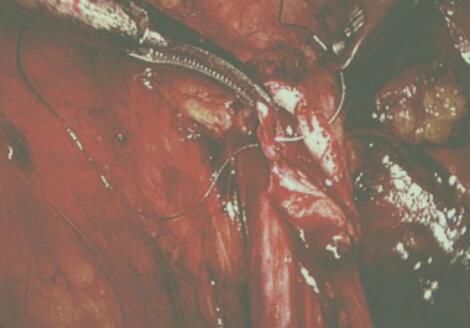

泌尿外科團(tuán)隊(duì)術(shù)中探查確診為腔靜脈后輸尿管,該病例系我院第一例,腹腔鏡下離斷輸尿管及修復(fù)重建,腹膜后腔操作空間較小,操作下方易傷及腔靜脈,手術(shù)風(fēng)險(xiǎn)高,手術(shù)難度巨大

在科室主任李世江的帶領(lǐng)下,步步為營進(jìn)行手術(shù)攻堅(jiān),顯露腎盂及上段輸尿管,向下游離下腔靜脈并明確輸尿管和下腔靜脈之關(guān)系。于近端輸尿管轉(zhuǎn)向處離斷輸尿管,將下腔靜脈后段輸尿管一位置下腔靜脈前面進(jìn)行端端吻合。